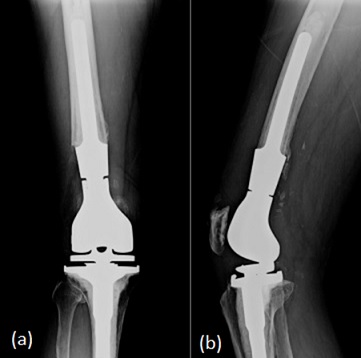

Distal Femoral Replacement (DFR) replaces the irreparably damaged distal femur with a prosthesis and is best reserved for fractures that cannot be reliably reconstructed (Figure 4). They are of particular use in those with severe comminution or in select periprosthetic injuries, especially in low-demand frail patients. Its key advantage lies in enabling immediate or early full weight bearing in these complex, unstable fracture patterns, thus avoiding prolonged restrictive mobilisation. However, DFR is a more extensive and costly operation with higher early complication rates and potential long term implant issues. When stable fixation remains feasible, it is generally preferred. Decisions should involve MDT discussion in experienced centres, with shared decision-making to align risks, benefits and patient goals.

Radiograph of a right distal femoral replacement. (a) Anterior View. (b) Lateral View Figure 4: Radiograph of a right distal femoral replacement. (a) Anterior View. (b) Lateral View [21].